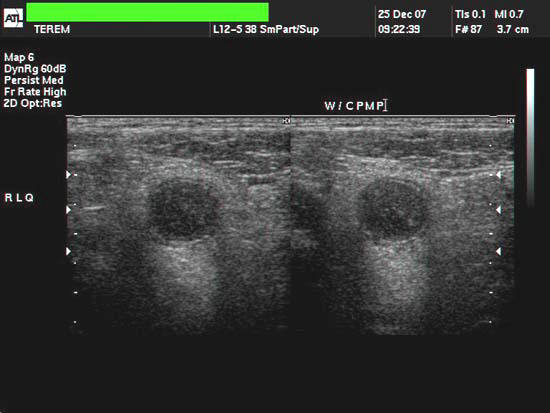

The above ultrasound images are of a young child (10yrs. old) with pain in the right iliac fossa. These images reveal a typical tubular structure with blind end, showing total diameter more than 6mm.(12 x 15 mm.). These sonographic images reveal hypoechoic content (purulent material) distending the appendix with an echogenic focus floating within it. The appendix was also non-compressible. Color flow imaging shows typical hyervascularity around the organ. These ultrasound images are diagnostic of acute appendicitis with appendicolith.( Images taken with a ATL (Philips HDI 3000 color doppler machine, courtesy of Mr. Shlomo Gobi, Israel).